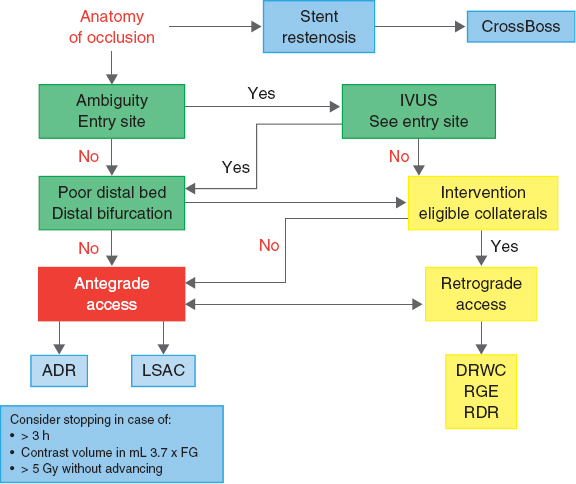

The Asia-Pacific algorithm37 integrates all techniques of coronary interventions on CTOs and establishes the strategy based on the anatomical findings. It also assesses the need to terminate a procedure (figure 2).

Figure 2. Modified algorithm (Asia-Pacific) to approach occlusions. ADR, antegrade dissection/re-entry; DRWC, direct retrograde wire crossing; GF, glomerular filtration; IVUS, intravascular ultrasound; LSAC, limited subintimal antegrade access; RDR, retrograde dissection/re-entry; RGE, retrograde guidewire escalation.

The Asia-Pacific algorithm takes into consideration the vessel architecture in the occlusion region; that is why a good bilateral injection is required to see the coronary arteries, even a coronary CT scan when necessary. Three basic parameters of the coronary anatomy are established (lengths > 20 mm do not determine the approach):

The ambiguity of the entry site.

The characteristics of the distal bed with respect to the occlusion site, assessing the quality of the distal bed and whether the CTO ends in a large bifurcation.

The presence of collaterals suitable for the retrograde access.

This algorithm also takes into consideration other factors like vessel tortuosity in the occlusion site, calcification, prior failed attempts, possible microchannels, and regions of reference (stents, calcium, contrast) to decide the strategy.